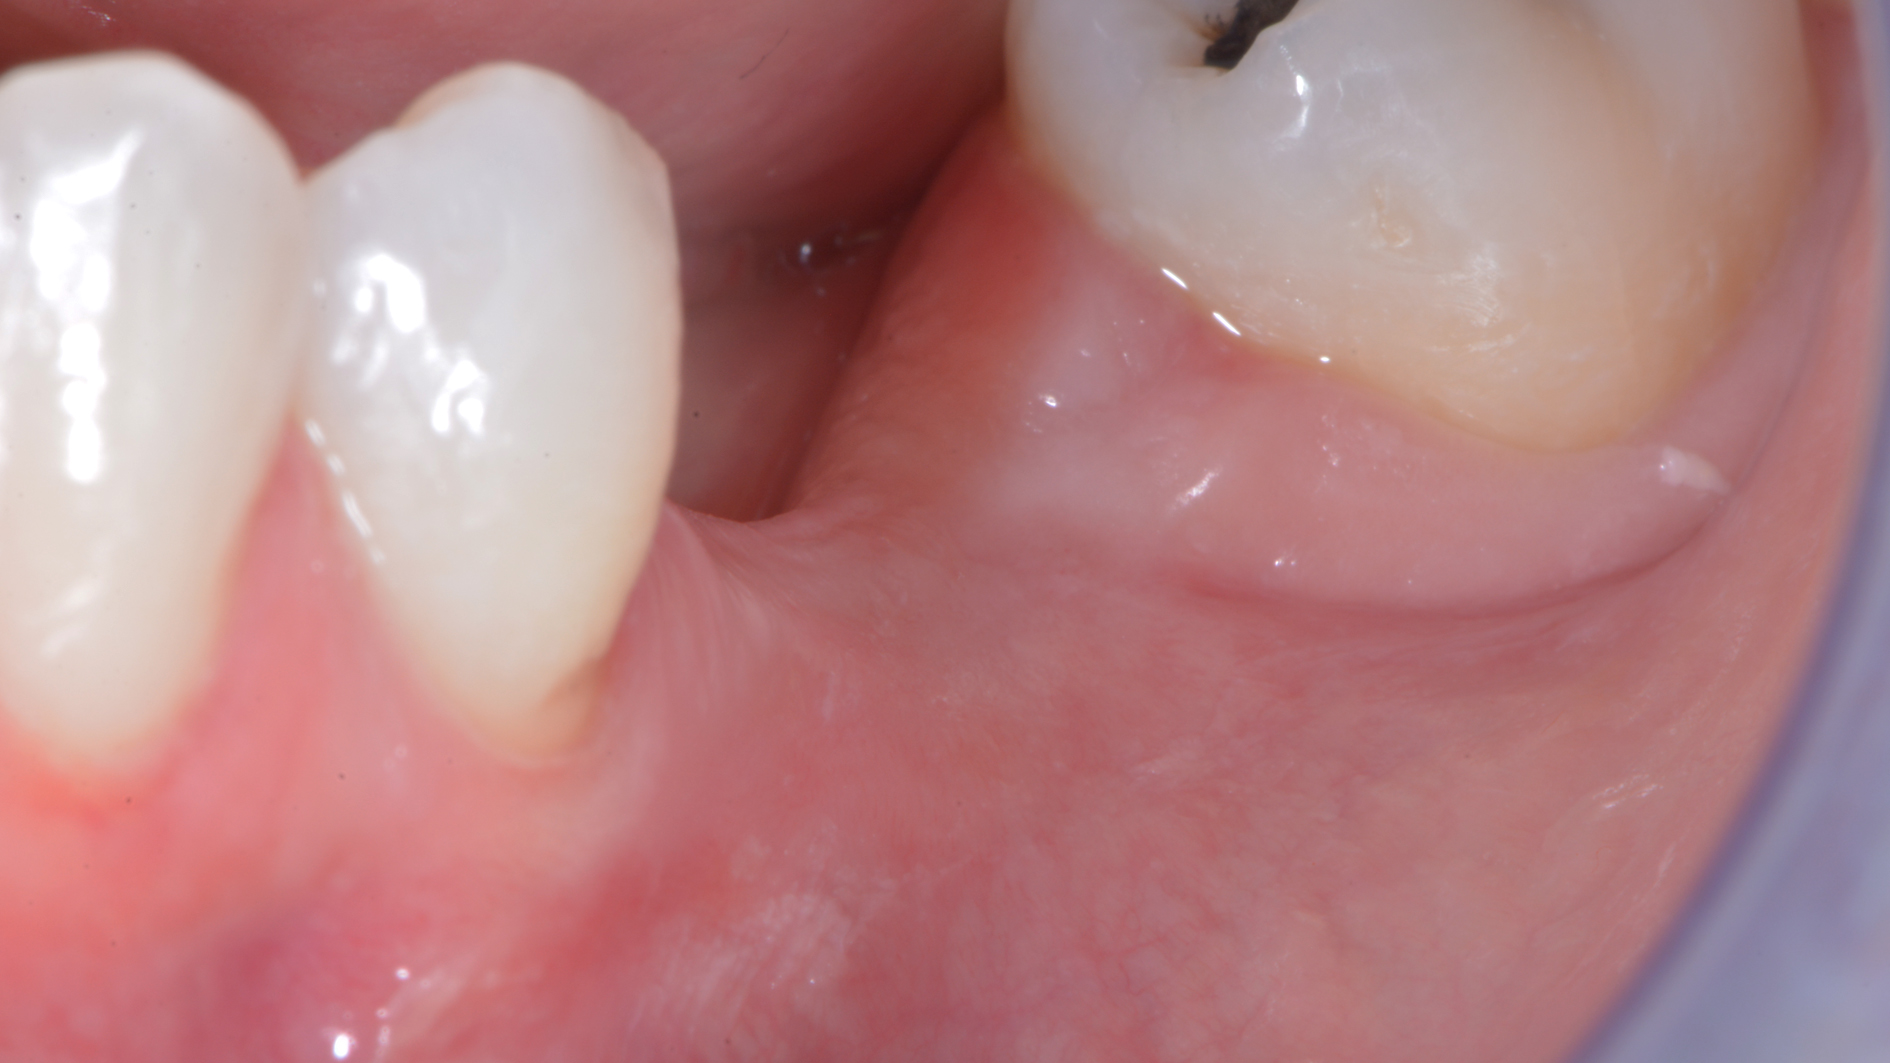

Come credi che si possa risolvere un caso come questo…

o come questo…

senza tecniche di chirurgia avanzata?

Ecco i risultati dei due casi:

Prendiamo un caso quotidiano. Quello di Alessia che ha 33 anni:

Puoi buttare giù due viti e metterci sopra due denti facendo una cosa molto lontana dalla natura.

O puoi riabilitare la paziente adeguatamente: